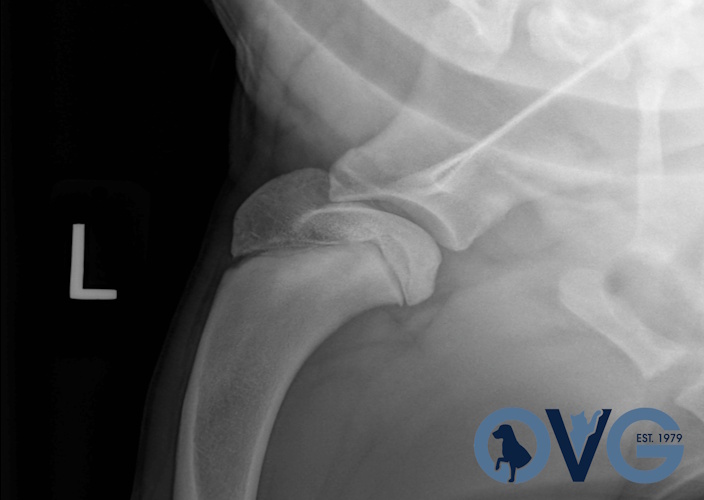

Hip Dysplasia in canines

Surgical Treatments of Hip Dysplasia